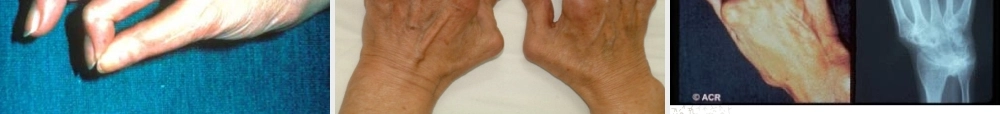

1类风湿关节炎Rheumathritisarthritis,RA2类风湿关节炎定义:RA是一种以累及周围关节为主的多系统性、炎症性、自身免疫性疾病。特征:慢性、对称性、周围性、多关节炎性病变关节表现关节外表现3流行病学几乎见于所有的种族和民族在多数人群中,类风湿关节炎的患病率为0.3-1.5%,我国的发病率为0.32-0.36%可发生在任何年龄,但发病高峰在35-50岁女性与男性患病的比例为3:14病因不清,可能细菌/病毒感染后—自身免疫反应遗传因素激素:雌激素水平升高。病因与发病机制5发病机制Ag巨噬细胞Th细胞活化T细胞B细胞细胞因子:IL-1、IL-6、TNF继续分泌:IL-2、IL-3、IL-4干扰素等(如促进胶原酶产生)免疫球蛋白:RF、其他的免疫球蛋白关节的滑膜炎血管炎6病理关节滑膜炎(synovitis):是基本病理改变急性期:渗出性和细胞浸润性,滑膜下有小血管扩张,内皮细胞肿胀,细胞间隙增大,间质有水肿和中性粒细胞浸润。慢性期:滑膜增生肥厚形成绒毛状突起,类似肿瘤的浸润性生长,造成关节破坏、畸形及功能障碍。血管炎可以发生在关节外的任何组织(动脉或静脉)内膜增生,管腔狭窄阻塞,类风湿结节是血管炎的一种表现(关节伸侧受压部)7病理8临床表现大部分起病缓慢,可有乏力、全身不适、发热、食欲不振等前驱症状。少数起病急骤,在数天内出现多个关节症状。•关节表现•关节外表现9关节表现典型表现为对称性多关节炎。主要侵犯小关节,尤其是手关节其次是趾、膝、踝、肘、肩等关节。滑膜炎症状关节结构破坏10关节表现•晨僵(morningstiffness)•痛与压痛•关节肿•关节畸形•关节功能障碍•特殊关节受累的表现11晨僵•概念:经过一段时间的静止或休息后,病人试图再活动某一关节时,感到局部不适、难以达到平时关节活动范围的现象。由于常在晨起时表现最明显,故又称晨僵。•出现在95%以上的患者;•持续时间与关节炎症成正比;•是疾病活动的指标之一;•主观性较强;12关节痛与压痛•关节痛是最早的关节症状•最常出现的部位:手关节如腕、掌指关节、近端指间关节其次是趾、膝、踝、肘、肩等关节•多呈对称性、持续性,但时轻时重•受累关节的皮肤可出现褐色色素沉着13关节肿胀•原因:•对称性•形状:梭形关节腔积液关节周围软组织炎症滑膜慢性炎症后肥厚141516关节畸形•尺侧偏斜•屈曲畸形•天鹅颈畸形•钮孔花畸形•其它畸形原因:1、滑膜炎绒毛破坏骨质结构,造成关节纤维性和骨性强直2、关节...